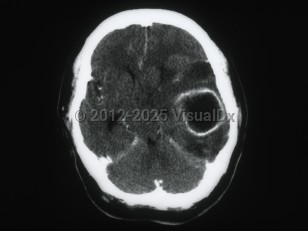

Brain abscess

Infection can be introduced via blood, from contiguous sites, or through trauma or surgery. Early cerebritis sets in following an inflammatory cell response (days 1-3), necrosis (days 4-9), and development of a collagen capsule (days 10-14).

Clinical features depend on the size and location of the lesion and vary from indolent to fulminant. Headache is the most common symptom. Rapid deterioration in mental status may suggest intraventricular rupture of the brain abscess. Less than 50% of patients present with the classical triad of headache, fever, and a focal neurological deficit. Clinical signs and symptoms in the immunocompromised host may be concealed due to lack of inflammatory response. A brain abscess due to Aspergillus spp. can commonly present with a stroke and often involves other organ systems. Other findings include altered mental status (confusion, lethargy, coma), nausea / vomiting, personality changes, and papilledema, and seizures may occur.